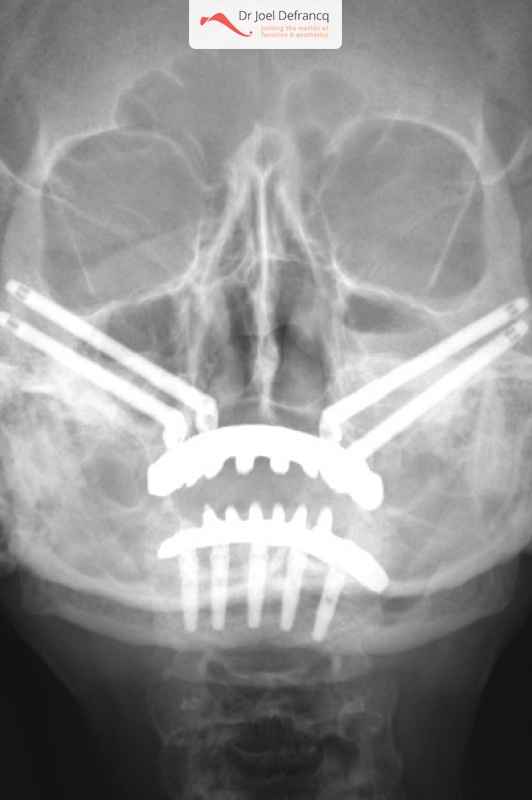

Paula: Dentale implantaten boven en onder / onmiddelijke belasting / Dentale zygoma implantaten

Behandeling tandheelkundige implantaten

- Vaste tanden op implantaten (bovenkaak)

- Vaste tanden op implantaten (onderkaak)

- Zygoma implantaten